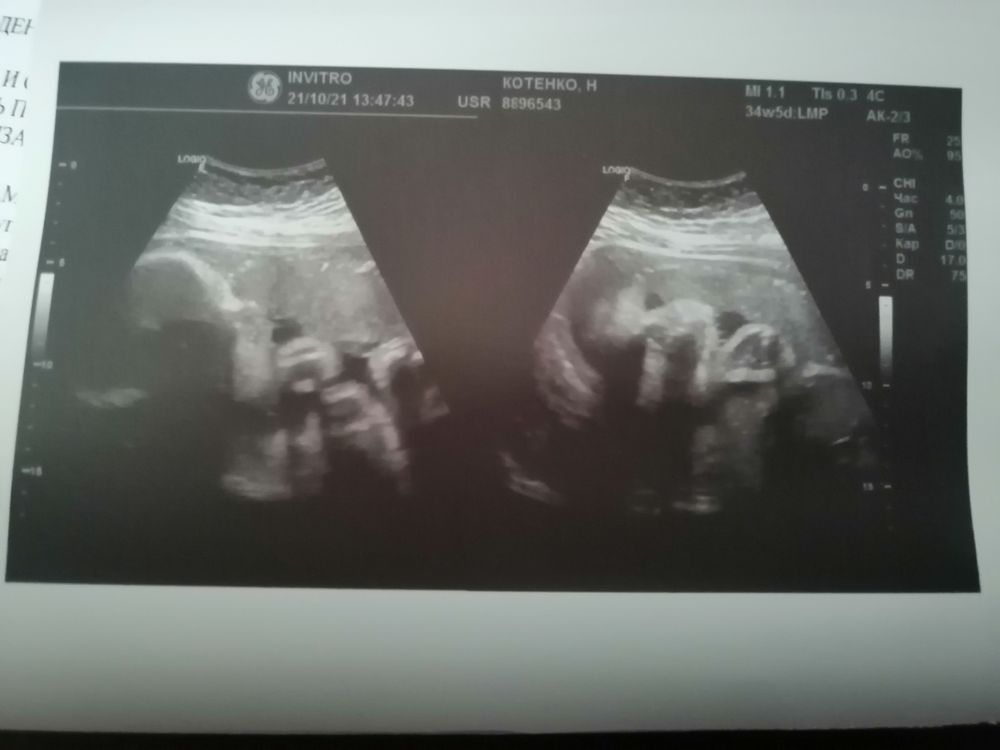

Вне плановое УЗИ (фото малышки)

УЗИ, КТГ, доплерВнезапно решила сходить посмотреть на малышку, а так же посмотреть шейку и маточные артерии. Шейка 37 мм, сомкнута, малышка в головном, поэтому и постоянные прострелы во влагалище. Плаценты правда немного не радует, 2 степени зрелости. Кровотоки в норме.

Боже, какие там щечки 😍😍😍 лежит такая вся спокойная, нежная, никаких резких движений. Пальчик сосёт 🥰